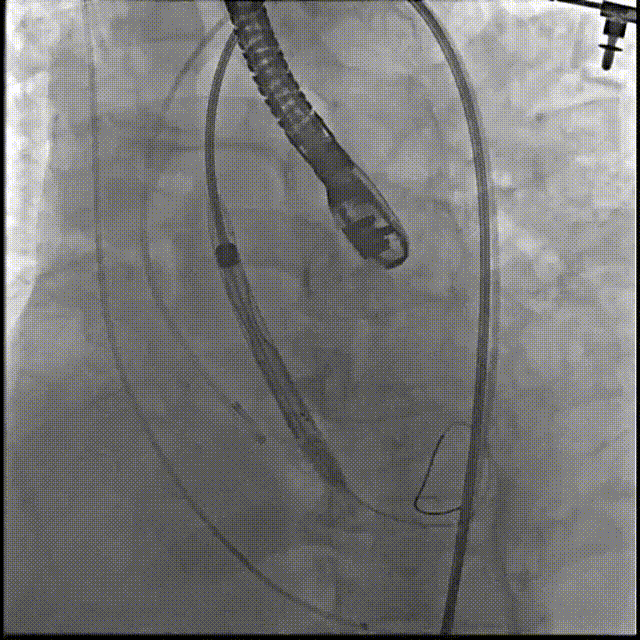

6.根据术前评估及球囊预扩情况,选择23mm沛嘉TaurusElite瓣膜进行植入,在150次/分保护起搏下0位释放瓣膜;

7.造影评估示瓣膜植入深度、工作形态良好、微量瓣周漏,遂予以全部释放;

8.超声平均跨瓣压差约0mmHg,存在少量瓣周漏,集中于自体瓣膜鱼嘴型开口伴有左室流出道钙化的一端;